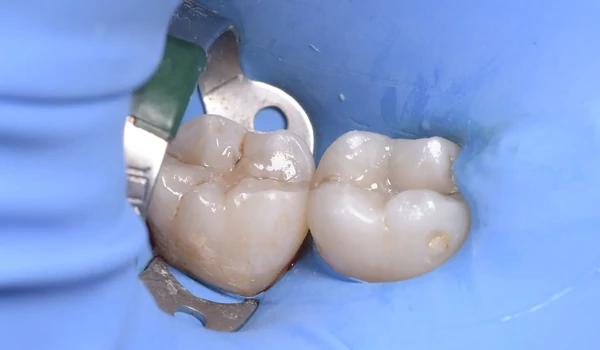

8. ábra A kezelés eredménye a kofferdam eltávolítása után. A restaurációk szépen illeszkednek a környező fogazathoz – színárnyalat és felületi fényesség. |